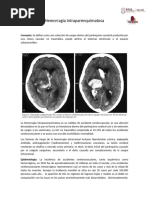

[Link]ía hipertensiva

La encefalopatía hipertensiva es un cuadro

clínico caracterizado por la presencia de

elevación aguda de la PA, cefalea intensa y

progresiva, náuseas, vómitos y alteraciones

visuales, que aparecen cuando los mecanismos

de autorregulación de la perfusión cerebral no

son capaces de ajustar el flujo sanguíneo.